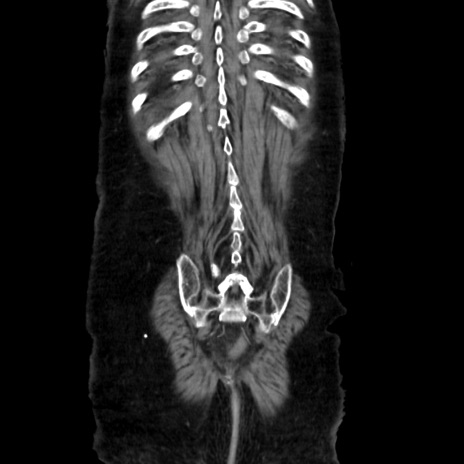

症例40(冠状断像)

矢状断像